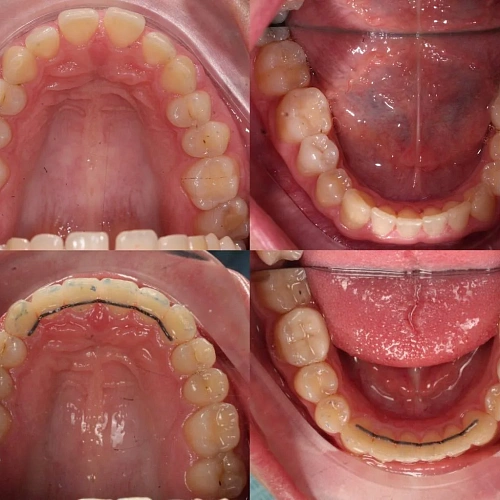

Нарушение соотношения челюстей и неправильное положение зубов — зубные ряды смыкались некорректно, зубы стояли со смещением.

Прозрачные элайнеры 3D Smile на обе челюсти. Выровнять зубы и нормализовать смыкание. Основной набор — 34 капы. Срок — около 2 лет.

Лечение заняло 32 месяца (февраль 2023 — октябрь 2025). Понадобился один дополнительный набор из 28 кап — итого 62 капы. Параллельно проводилась профессиональная гигиена.

Проблема: Пациентку беспокоило неправильное смыкание зубов и их положение — ряды не сходились как нужно, зубы стояли со смещением. Это влияло и на внешний вид, и на то, как распределялась нагрузка при жевании.

Решение: Поставили прозрачные элайнеры 3D Smile на обе челюсти. Начали с набора из 34 кап, но в процессе стало понятно, что для полной коррекции нужна доработка — заказали дополнительный набор из 28 кап. Это нормальная ситуация: организм реагирует на перемещение зубов индивидуально, и заранее предсказать точное количество кап до последней штуки невозможно. В итоге 62 капы за 32 месяца — зубы встали на место, смыкание пришло в норму. Параллельно следили за гигиеной, чтобы дёсны оставались здоровыми на протяжении всего лечения.